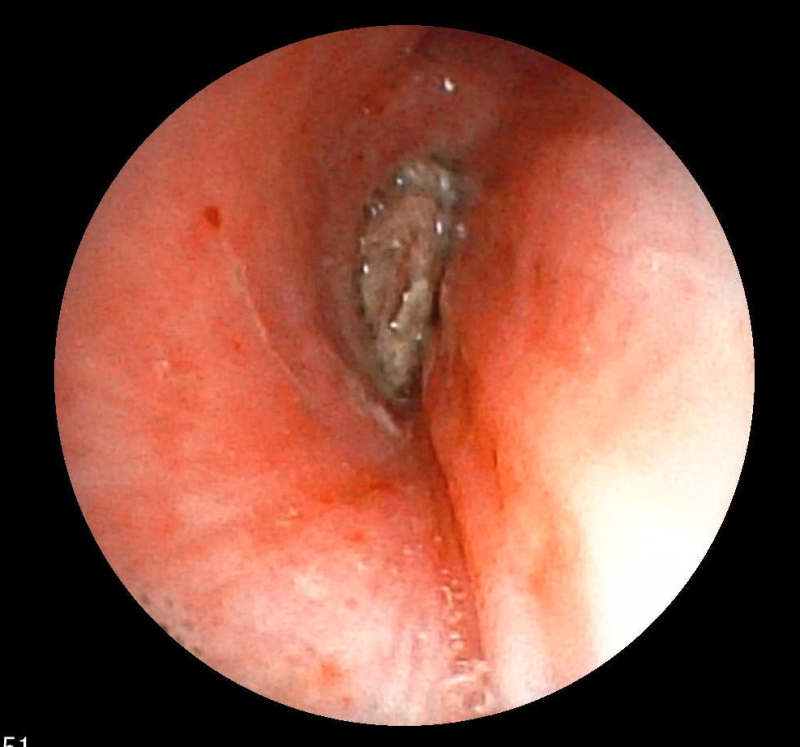

Hình ảnh dị vật góc cạnh khoảng 1cm là hạt kha tử hình bầu dục, bề mặt trơn nhẵn, hai đầu nhọn nằm chắn, gây bít tắc trong lòng phế quản gốc phải trên màn hình nội soi phế quản

Ekip của bác sĩ CKI Phạm Thị Út Trang – Phó Trưởng Khoa Nội hô hấp đã phối hợp với bác sĩ gây mê hồi sức đã nhanh chóng tiến hành nội soi phế quản ống mềm, phát hiện dị vật góc cạnh khoảng 1cm là hạt kha tử hình bầu dục, bề mặt trơn nhẵn, hai đầu nhọn nằm chắn, gây bít tắc trong lòng phế quản gốc phải, ngay sát vị trí chia nhánh phế quản phân thùy- khu vực giải phẫu hẹp, góc rẽ nhánh phức tạp khiến việc gắp dị vật gặp khó khăn.  Ekip nội soi can thiệp đã khéo léo tiếp cận và thành công gắp dị vật ra khỏi lòng phế quản. Sau can thiệp, sức khỏe của bệnh nhân ổn định, thở dễ dàng, không còn cảm giác tức ngực, được xuất viện sau 24h theo dõi.